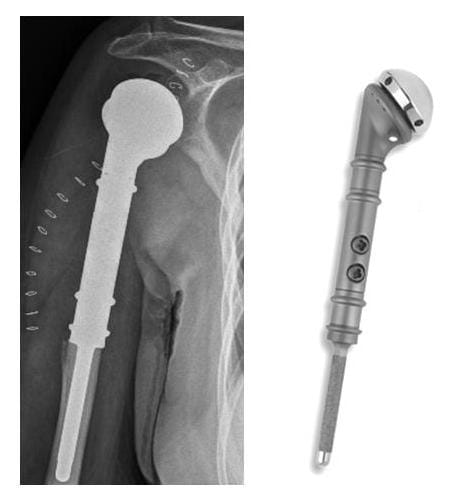

Diese Sonderprothese wird eingesetzt, wenn das Gelenk und der Oberarm von einer Tumorerkrankung befallen sind und ein Erhalt der Gelenk- und Armfunktion durch andere Behandlungsmethoden nicht mehr möglich ist. Da in der Regel auch Teile der Muskulatur und Sehnen befallen sind, bleibt die Schulterfunktion eingeschränkt. Ziele sind daher in erster Linie Schmerzfreiheit, ein stabiler Arm und somit ein Erhalt der Unterarm- und Handfunktion. Der modulare Aufbau erlaubt eine weitgehend genaue Wiederherstellung der Armlänge. In einigen Fällen kann die Prothese auch als inverse Schulterprothese eingesetzt werden.

Röntgenbild Tumorprothese

Röntgenbild einer Tumorprothese (Orthopädie, Klinikum Bielefeld)

Prothesenmodell (Fa. Implantcast)